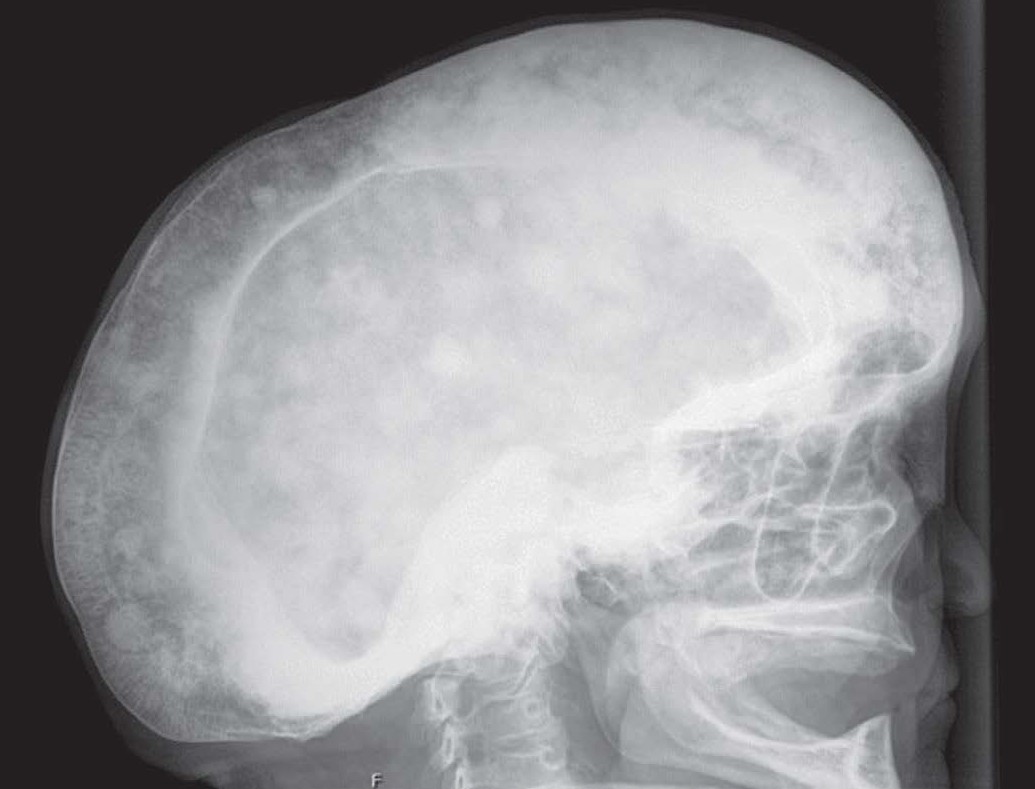

• From Bone to Tone: Paget’s Disease of the Skull

Rosélia Lima, Guilherme, Pedro

191-192

DOI: https://doi.org/10.60591/crspmi.481